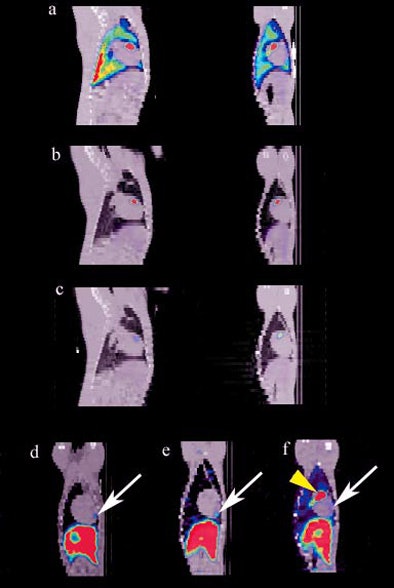

| Combined SPECT/CT images on days 1 (A), 2 (B), and 7 (C) in a dog that demonstrated focal uptake in the anterior midventricular region of the heart. D to F, at the last imaging time point (days 5 to 8), a region of MSC uptake (arrow) is shown in three representative animals. All images courtesy of Kraitchman et al, Johns Hopkins University. |

The SPECT/CT images revealed the redistribution of radiolabeled stem cells from their initial landing point in the lungs to the heart, as well as to nontarget organs such as the liver, kidney, and spleen. Since the cells redistributed to other areas of the body, Kraitchman and her colleagues developed specialized reconstruction algorithms to ensure that they were seeing the heart in the images they collected.